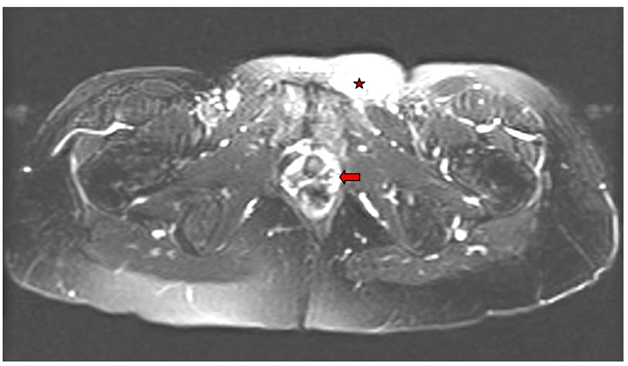

On examination, the patient was comfortable, afebrile and vital signs were within normal limits. A 3cm left suprapubic mass without fluctuation was noted. There was no evidence of local inflammation or abscess. Speculum exam revealed a short vagina due to previous radiation, with no evidence of any foreign body and no evidence of vaginitis. On bimanual examination there were no appreciable vaginal or pelvic masses. A pelvic MRI revealed a nonspecific suprapubic left subcutaneous inflammation extending to the sub-vaginal tissue (Figure 1). The clinical presentation was highly suggestive of local reaction to the porcine dermis arm on the left side. Because of the patient’s history of cervical cancer, gynecologic oncology was consulted to rule out recurrence of cervical cancer. The surgical team was also consulted to rule out a hernia.

Figure 1 T2 noncontrast Axial MRI of the pelvis showing nonspecific subcutaneous edema of the left suprapubic area (asterisks) and sub-vaginal tissues (arrow).